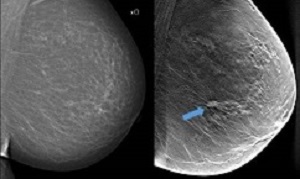

In traditional mammography screening, all breast tissue is captured in a single image. Breast tomosynthesis, on the other hand, is three-dimensional and works according to the same principle as what is known as tomography. This means that several low-dose x-ray images are taken of the breast from different angles, which are reconstructed by a computer to show thin layers of the breast. With more and improved image information and less overlapping tissue structures, the chance of detecting tumours increases.

Background: Digital breast tomosynthesis is an advancement of the mammographic technique, with the potential to increase detection of lesions during breast cancer screening. The main aim of the Malmö Breast Tomosynthesis Screening Trial (MBTST) was to investigate the accuracy of one-view digital breast tomosynthesis in population screening compared with standard two-view digital mammography.

Interpretation: Breast cancer screening by use of one-view digital breast tomosynthesis with a reduced compression force has higher sensitivity at a slightly lower specificity for breast cancer detection compared with two-view digital mammography and has the potential to reduce the radiation dose and screen-reading burden required by two-view digital breast tomosynthesis with two-view digital mammography.